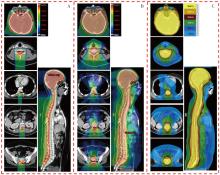

目的探索质子调强放疗(IMPT)、光子固定野调强放疗(IMRT)以及光子螺旋断层放疗(TOMO)技术应用于儿童全中枢神经系统肿瘤照射的剂量学特点。方法以1例山东省肿瘤防治研究院(山东省肿瘤医院)临床诊断为非典型畸胎样/横纹肌样瘤、脊膜转移、脑膜转移,行全脑全脊髓放疗(CSI)的14岁儿童患者靶区为例,根据靶区的临床处方和危及器官(OAR)的限值要求,分别设计IMPT、IMRT和TOMO计划。对各计划靶区的适形指数(CI)、均匀性指数(HI)和梯度指数(GI),以及正常组织的剂量体积指标进行评估,对比3类计划的剂量学特点。结果IMPT计划的CI(0.71)、HI(0.05)和GI(3.13)均与IMRT计划(0.80、0.08、3.14)相当,TOMO计划的HI(0.03)、GI(2.54)较优,且均在临床接受范围内。IMPT计划中并行器官受照剂量低于IMRT和TOMO计划;IMPT计划中双肺V5为2.9%,IMRT为37.6%,TOMO为43.5%;IMPT计划的肝脏Dmean为0.01 Gy(RBE),IMRT计划为6.12 Gy,TOMO计划为6.39 Gy;IMPT计划中膀胱、直肠、股骨头均没有受量,而在IMRT和TOMO计划中均有低剂量辐射。对于毗邻靶区和包含在靶区内的串行器官,IMPT计划中脊髓和脑干的Dmax分别为39.89和39.88 Gy(RBE),IMRT计划分别为39.43 和38.59 Gy,TOMO计划分别为38.41和37.69 Gy。IMPT计划中低剂量区显著优于光子放疗计划,其中患者体内10%的处方剂量区域所占的绝对体积IMPT计划较IMRT计划减少了70.10%,较TOMO计划减少了76.96%;30%的处方剂量体积IMPT计划较IMRT计划减少了53.49%,较TOMO计划减少了62.51%;50%的处方剂量体积IMPT计划较IMRT计划减少了39.06%,较TOMO计划减少了42.23%。结论在儿童CSI中,IMPT计划的低剂量区与并行OAR受照剂量显著少于IMRT和TOMO计划。3种计划的CI、HI和GI均能满足临床要求。对于毗邻靶区和包含在靶区内的串行器官,IMPT计划的Dmax可能比IMRT和TOMO计划剂量更高。

ObjectiveTo explore the dosimetric characteristics of intensity modulated proton therapy (IMPT),intensity modulated radiation therapy (IMRT) and tomotherapy (TOMO) techniques applied in the irradiation of pediatric whole central nervous system tumors.MethodsTaking the target area of a 14-year-old pediatric patient clinically diagnosed with atypical teratoid/rhabdomyoid tumor,meningeal metastasis by Shandong Cancer Hospital and Institute,and undergoing craniospinal irradiation (CSI) as an example,IMPT,IMRT and TOMO plans were designed respectively based on the clinical prescription of the target area and the limit requirements of organs at risk (OARs). The conformal index (CI),homogeneity index (HI) and gradient index (GI) of each planning target volume,as well as the dose volume index of normal tissues,were evaluated to compare the dosimetric characteristics of the three types of plans.ResultsThe CI (0.71),HI (0.05) and GI (3.13) of the IMPT plan were comparable to those of IMRT plan (0.80,0.08,3.14). The HI (0.03) and GI (2.54) of the TOMO plan were excellent,which were all within the clinically acceptable range. The irradiation dose to parallel organs in the IMPT plan was lower than that in the IMRT and TOMO plan. In the IMPT plan,V5of lungs was 2.9%,IMRT plan was 37.6%,and TOMO plan was 43.5%. The Dmeanof liver in the IMPT plan was 0.01 Gy(RBE),IMRT plan was 6.12 Gy,and TOMO plan was 6.39 Gy. In the IMPT plan,none of the bladder,rectum,and femoral head received the dose,while there was low-dose radiation in both IMRT and TOMO plan. For serial organs adjacent to and within the target area,the Dmaxof spinal cord and brainstem in IMPT plan was 39.89 and 39.88 Gy(RBE),respectively; in IMRT plan,they were 39.43 and 38.59 Gy,respectively; and in TOMO plan,they were 38.41 and 37.69 Gy,respectively. The low-dose area in the IMPT plan was significantly better than the photon radiotherapy plans. Among them,the absolute volume IMPT plan occupied by 10% of the prescribed dose area in the patient's body was reduced by 70.10% compared with IMRT plan and 76.96% compared with TOMO plan; the 30% prescribed dose volume IMPT plan was reduced by 53.49% compared with IMRT plan and 62.51% compared with TOMO plan; the 50% prescribed dose volume IMPT plan was reduced by 39.06% compared with IMRT plan and 42.23% compared with TOMO plan.ConclusionsThe IMPT plan demonstrated significantly reduced low-dose exposure and lower doses to parallel OARs compared to both IMRT and TOMO plans in pediatric CSI. The CI,HI and GI of the three plans can all meet the clinical requirements. However,for serial organs adjacent to and within the target area,the Dmaxof the IMPT plan may be higher than that of IMRT and TOMO plans.